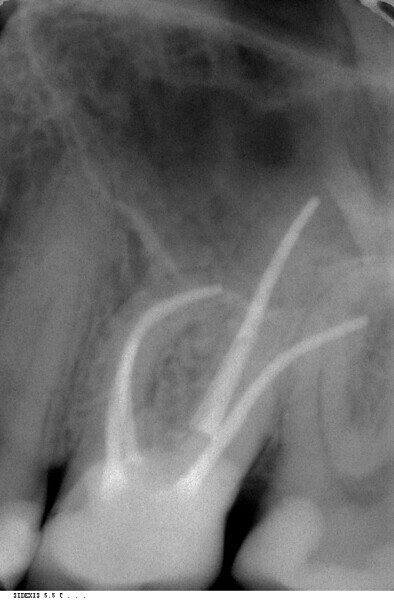

Endodontic follow-up in strongly curved root canals